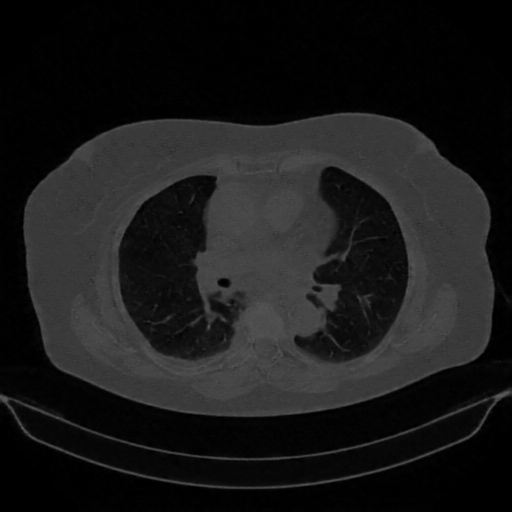

Targeted Slice 70 - Lung Window Analysis (Generated vs Real Venous)

0.660

Lung SSIM

118.4

Lung RMSE

51.5

Lung MAE

Average Lung Window Metrics Across All Slices (161 slices) - Generated vs Real Venous

0.663

Lung SSIM (Avg)

109.6

Lung RMSE (Avg)

49.1

Lung MAE (Avg)

Generated VENOUS CT scan (A→B translation)

Lung window (WL -600, WW 1500 β†’ Low βˆ’1350, High +150)